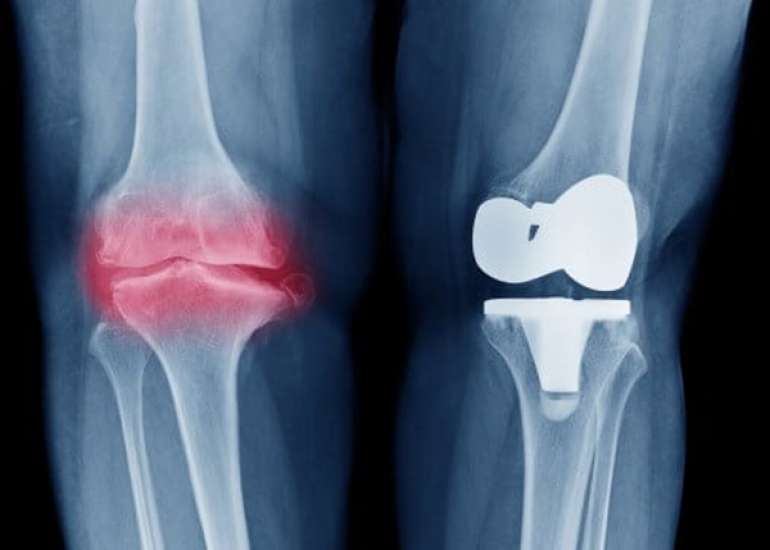

Director (Orthopaedics & Joint Replacement) & Head of Unit-1, Max Smart Super Speciality Hospital, Saket